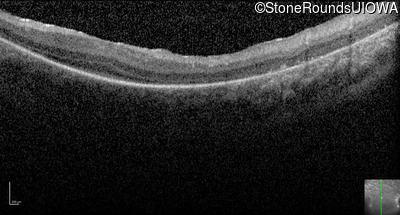

Optical Coherence Tomography - Left -

Light Perception

Exemplar

Expanded OCT Stack

×